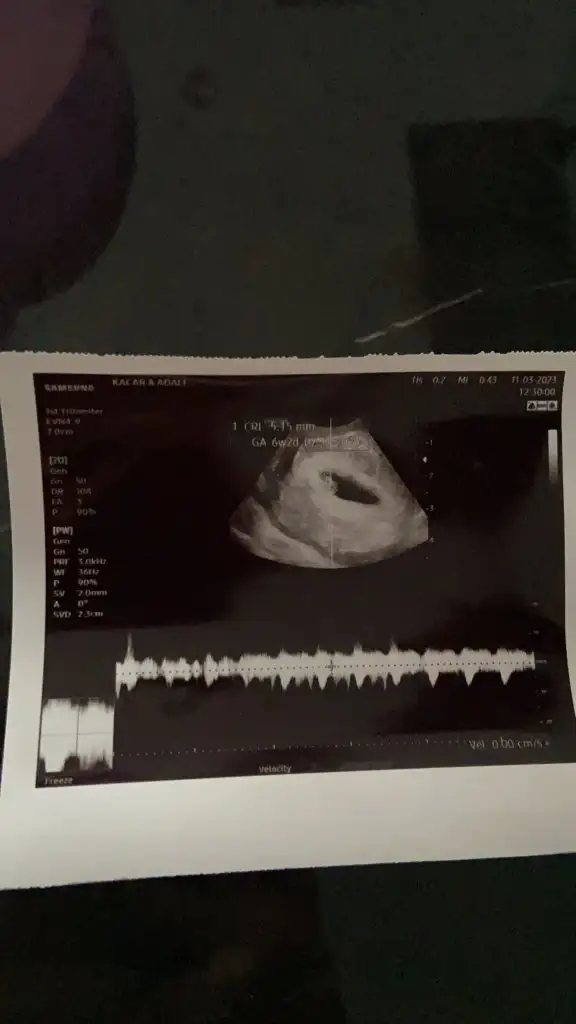

Merhaba kızlar çok şükür evlatlarımız büyüyor ve sağlıklılar rabbim isteyen herkese nasip etsin. Artık korkularımı bırakıyorum. Rabbim kötülüklerden korusun hepimiz yavrularımızı kucağımıza almayı nasip etsin. Ultrasona göre 3 gün önden gidiyor dedi bir sorun yoktur umarım. Ve bize muaynede kolunu oynatırken denk geldi çok farklı bi duyguydu. Rabbime şükürler olsun. 3 hafta sonra tekrar çağırdı sağlık ocağında yapılması gereken testleri istedi dr. 2 tane olan testi karşılamıyor sağlık ocağı rubella ve toxoplazma bunlar çok önemlimi dikkat etmek gerekli bir bilgi varmı. Birde sağlık ocağı hamilelik takibi yapılacak dendi mayıs ayı gibi tetenoz aşısı varmış yqpılması zorunlumu. Cinsiyet ne zaman net öğreniriz.